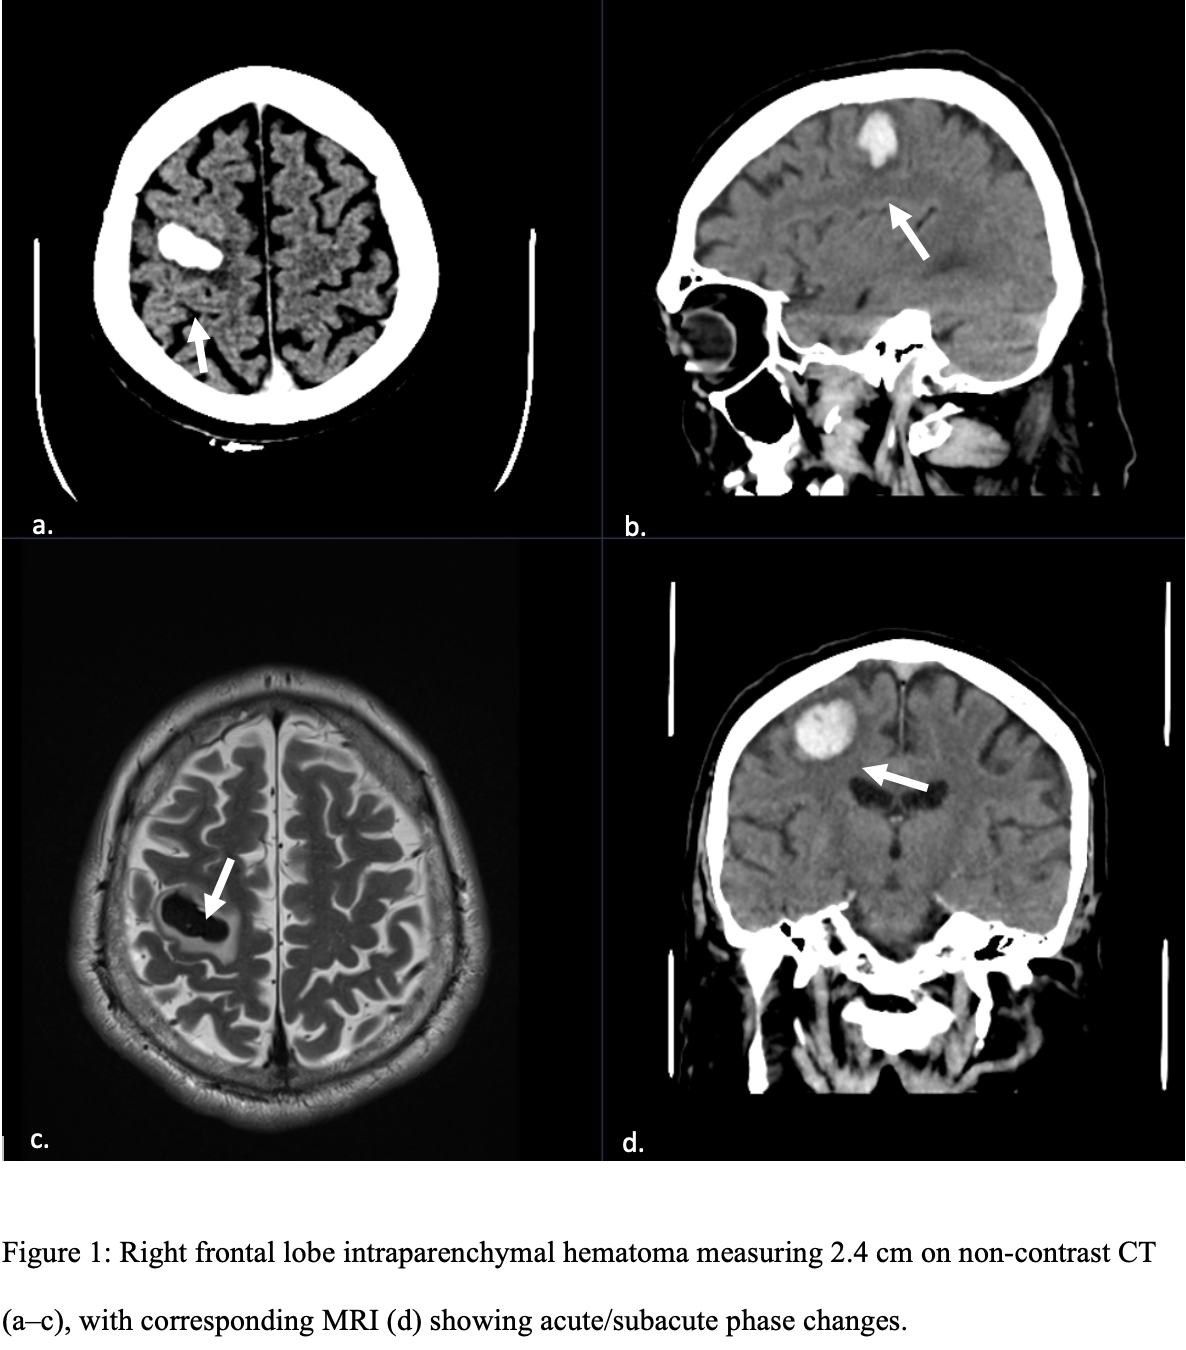

While opsoclonus-myoclonus-ataxis (dancing eye-dancing feet syndrome) may seem rare and complex, its early identification in the ED can be life‑altering. When faced with an unusual movement disorder a